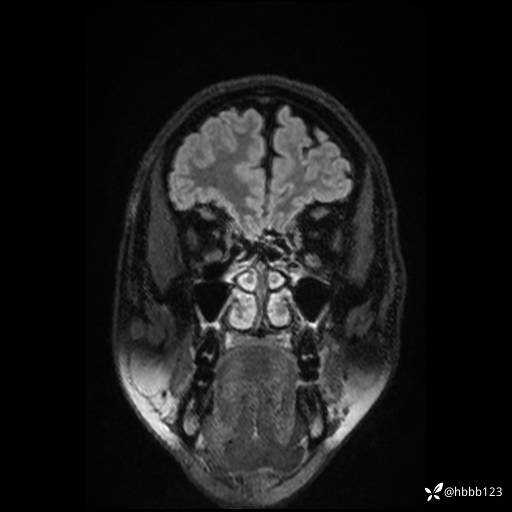

CUBE FLAIR横断位: